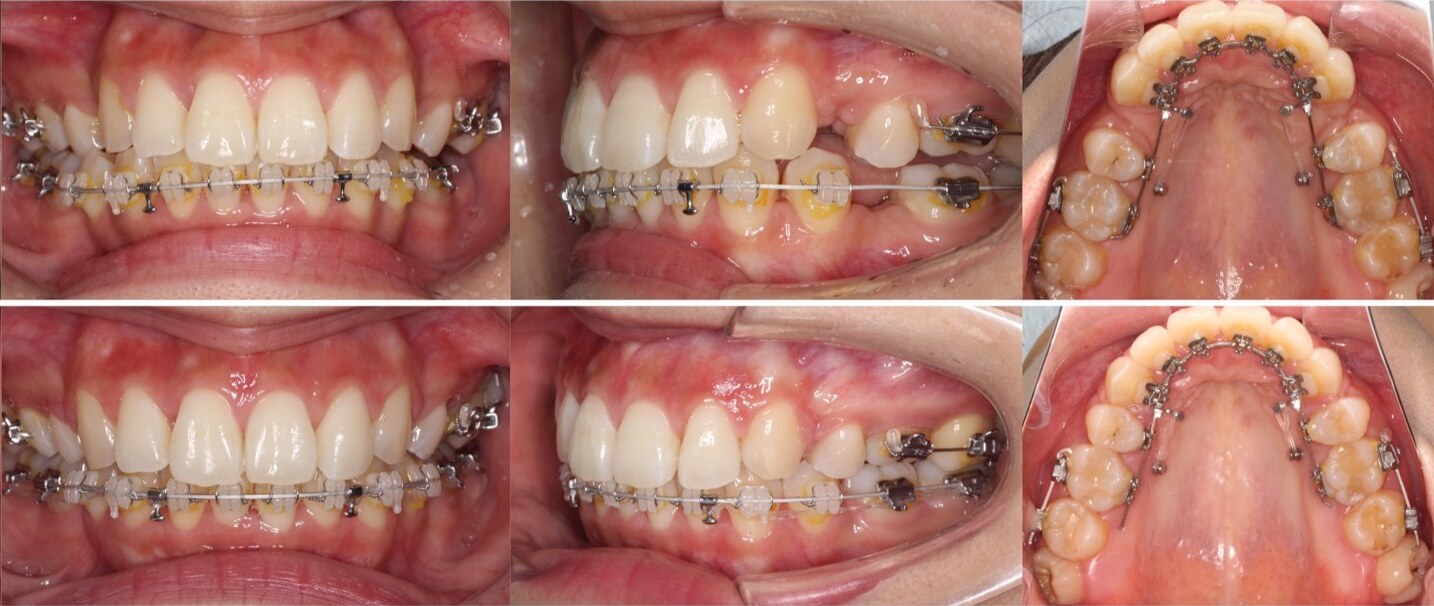

20代女性・ハーフリンガル矯正装置・抜歯

<顔のビフォーアフター>

<症例概要>

主訴:出っ歯を治したい

年齢・性別:20代女性

住まい:千葉県佐倉市

症状:上顎前突・過蓋咬合

治療方針:抜歯空隙の閉鎖(最大固定)

治療装置:ハーフリンガル矯正装置(上のみ裏側装置)

固定装置:口蓋側壁アンカースクリューx2

抜歯:上第一小臼歯(計2本)

治療期間:2年3か月

リテーナー:上下クリアタイプ+フィックスタイプ

治療費用:1,495,000(税込)

代表的副作用:痛み・治療後の後戻り・歯根吸収・歯髄壊死・歯肉退縮

▶︎その他の副作用

著しく上の前歯が突出しているケースです。審美的な矯正装置を希望されたのでハーフリンガル矯正で治療をしました。歯科矯正用アンカースクリューを併用する事で抜歯したスペースを全て前歯を引っ込める事に使用できました。 過蓋咬合が併発している上顎前突は下の歯並びは表側矯正装置の方がコントロールしやすいと言えます。